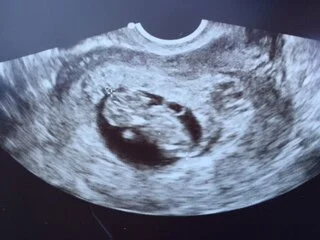

Then came the hard part:  waiting for the pregnancy test.  I know I drove my friends crazy while I waited.  And I totally didn't wait like I was supposed to.  I was testing early on and knew days before the blood test that it would be positive.  Still, I nervously awaited the rests.  118.  That was a Friday.  The number needed to at least double by Monday.  This is where things always went wrong before.  We never passed the second blood draw.  Our numbers always dropped.  And even though we "took the ferry instead of the tunnel" as my husband put it and things were different than before, my heart was choked with fear.  Usually I can dream big and imagine grand outcomes.  My heart would not allow it and I could not even imagine a world where those numbers would double.  And yet they did. 380.  And for the first time I began to feel hope for our child.  The next step was the ultrasound at 7 weeks.  Here they would determine how many babies I was carrying, and they would look for the heartbeat, measure, and determine a due date.  After reading account after account of women going in and there being no heartbeat I was once again gripped with fear.  We prayed.  Friends prayed.  I specifically asked for strong pregnancy symptoms to reassure my heart that all way well.  And that prayer was answered.  My husband and I made an agreement that I was not allowed to complain about my symptoms and instead we would give praise to the Lord for answering our prayers.  At that first ultrasound I was sick with worry, but for no reason.  Within seconds we could see the heartbeat flicker on the screen.  131 beats/minute.  perfect.  The doctor hooked up the audio and we could hear it.  I can't describe the elation in our hearts at that sound.  I was scheduled to come back at 10 weeks to check on progress and to graduate to the normal OB doctor.

4 days later we had an unwelcome development.  I had started bleeding.  Having never had any bleeding or spotting with my surviving children, I was convinced I was miscarrying.  It was a beautiful weekend.  I had got up, exercised, grocery shopped, did yard work, and we were hosting a cook out.  I have several other people over when it started.  I withdrew to my room for a spell, and reemerged after I composed myself.  The evening was winding down and we tried to enjoy the last moments with our company.  As soon as they left I retired to my bedroom.  My husband got on the phone with the doctor, and our 16 year old daughter cleaned up the aftermath of the party.  The doctor was not too concerned based on our description.  He said it was quite common and usually doesn't mean anything other than I may have overdone it a little.  He suggested taking it easy and said to come in for an ultrasound during the week if it continued.  I was slightly relieved, but very much on edge.  My husband put me on full bedrest for the remainder of the weekend, and I did not object.  Friends and family were enormously caring and helpful during those scary days.  The bleeding did subside, but spotting persisted.  We went in for another ultrasound and there was our little gummy bear, with heart as strong as before.  They had no explanation for the bleeding but said to keep them informed.  The following week, the spotting continued and we went in again for reassurance.  I am so thankful for the doctor's office for the support they gave.  They did not protest my insistence on multiple scans and were very understanding of the fear we felt.  They treated us with great compassion and dignity.  Once again all was well and we even got to see the baby wiggle.  The doctor then suggested that it could be from what's called a subchorionic clot, which is where the sac separates a little from the uterine wall, but could not tell from the ultrasound as it could be too small to see.  He still wanted to see me again at the 10 week mark, which was only a week away.  At 10 weeks, we came in and once again everything looked great.  The spotting was mostly gone by then and he could finally see a subchorionic clot.  He pointed it out and said it was "well-organized" or healed.  It was such a relief to have an answer, to have the complication resolved, and to see our little one and its heartbeat once more.  And at this ultrasound our baby had moved from simple wiggling to total dance party boogying!!  Doctor exclaimed, "that is an active one!!"  Sounds like we will have our work cut out for us.